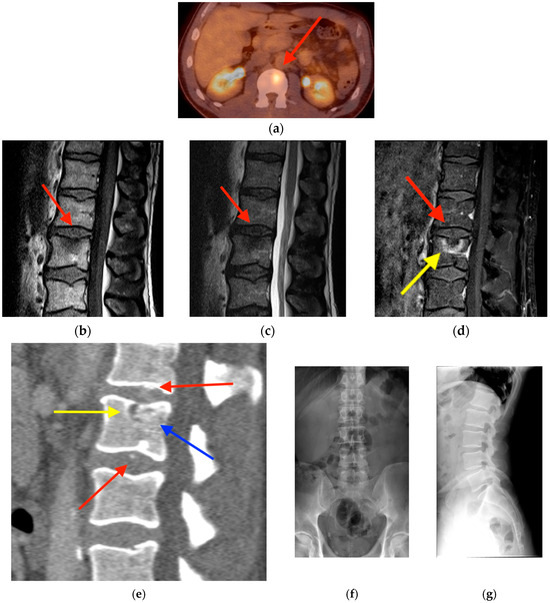

2.1. Fracture

- Chung, Y.K.; Lee, Y.K.; Yoon, B.H.; Suh, D.H.; Koo, K.H. Pelvic Insufficiency Fractures in Cervical Cancer After Radiation Therapy: A Meta-Analysis and Review. In Vivo 2021, 35, 1109–1115. [Google Scholar] [CrossRef]

- Blomlie, V.; Rofstad, E.K.; Talle, K.; Sundfør, K.; Winderen, M.; Lien, H.H. Incidence of radiation-induced insufficiency fractures of the female pelvis: Evaluation with MR imaging. AJR Am. J. Roentgenol. 1996, 167, 1205–1210. [Google Scholar] [CrossRef]

- Abe, H.; Nakamura, M.; Takahashi, S.; Maruoka, S.; Ogawa, Y.; Sakamoto, K. Radiation-induced insufficiency fractures of the pelvis: Evaluation with 99mTc-methylene diphosphonate scintigraphy. AJR Am. J. Roentgenol. 1992, 158, 599–602. [Google Scholar] [CrossRef]

- Salavati, A.; Shah, V.; Wang, Z.J.; Yeh, B.M.; Costouros, N.G.; Coakley, F.V. F-18 FDG PET/CT findings in postradiation pelvic insufficiency fracture. Clin. Imaging 2011, 35, 139–142. [Google Scholar] [CrossRef]

- Zhong, X.; Zhang, L.; Dong, T.; Mai, H.; Lu, B.; Huang, L.; Li, J. Clinical and MRI features of sacral insufficiency fractures after radiotherapy in patients with cervical cancer. BMC Womens Health 2022, 22, 166. [Google Scholar] [CrossRef]